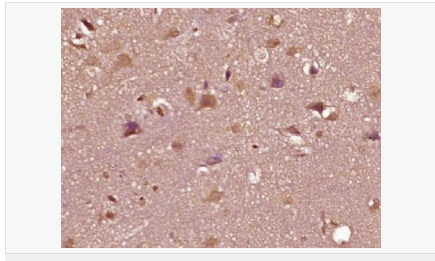

| 產品介紹 | The androgen receptor gene is more than 90 kb long and codes for a protein that has 3 major functional domains: the N-terminal domain, DNA-binding domain, and androgen-binding domain. The protein functions as a steroid-hormone activated transcription factor. Upon binding the hormone ligand, the receptor dissociates from accessory proteins, translocates into the nucleus, dimerizes, and then stimulates transcription of androgen responsive genes. This gene contains 2 polymorphic trinucleotide repeat segments that encode polyglutamine and polyglycine tracts in the N-terminal transactivation domain of its protein. Expansion of the polyglutamine tract causes spinal bulbar muscular atrophy (Kennedy disease). Mutations in this gene are also associated with complete androgen insensitivity (CAIS). Two alternatively spliced variants encoding distinct isoforms have been described. [provided by RefSeq, Jul 2008] Function: Steroid hormone receptors are ligand-activated transcription factors that regulate eukaryotic gene expression and affect cellular proliferation and differentiation in target tissues. Transcription factor activity is modulated by bound coactivator and corepressor proteins. Transcription activation is down-regulated by NR0B2. Activated, but not phosphorylated, by HIPK3 and ZIPK/DAPK3. [ENZYME REGULATION] AIM-100 (4-amino-5,6-biaryl-furo[2,3-d]pyrimidine) suppresses TNK2-mediated phosphorylation at Tyr-267. Inhibits the binding of the Tyr-267 phosphorylated form to androgen-responsive enhancers (AREs) and its transcriptional activity. Subunit: Binds DNA as a homodimer. Part of a ternary complex containing AR, EFCAB6/DJBP and PARK7. Interacts with HIPK3 and NR0B2 in the presence of androgen. The ligand binding domain interacts with KAT7/HBO1 in the presence of dihydrotestosterone. Interacts with EFCAB6/DJBP, PELP1, PQBP1, RANBP9, RBAK, SPDEF, SRA1, TGFB1I1, ZNF318 and RREB1. Interacts with ZMIZ1/ZIMP10 and ZMIZ2/ZMIP7 which both enhance its transactivation activity. Interacts with SLC30A9 and RAD54L2/ARIP4. Interacts via the ligand-binding domain with LXXLL and FXXLF motifs from NCOA1, NCOA2, NCOA3, NCOA4 and MAGEA11. The AR N-terminal poly-Gln region binds Ran resulting in enhancement of AR-mediated transactivation. Ran-binding decreases as the poly-Gln length increases. Interacts with HIP1 (via coiled coil domain). Interacts (via ligand-binding domain) with TRIM68. Interacts with TNK2. Interacts with USP26. Interacts with RNF6. Interacts (regulated by RNF6 probably through polyubiquitination) with RNF14; regulates AR transcriptional activity. Interacts with PRMT2 and TRIM24. Interacts with GNB2L1/RACK1. Interacts with RANBP10; this interaction enhances dihydrotestosterone-induced AR transcriptional activity. Interacts with PRPF6 in a hormone-independent way; this interaction enhances dihydrotestosterone-induced AR transcriptional activity. Interacts with STK4/MST1. Interacts with ZIPK/DAPK3. Interacts with LPXN. Interacts with MAK. Part of a complex containing AR, MAK and NCOA3. Subcellular Location: Nucleus. Cytoplasm. Note=Predominantly cytoplasmic in unligated form but translocates to the nucleus upon ligand-binding. Can also translocate to the nucleus in unligated form in the presence of GNB2L1. Tissue Specificity: Isoform 2 is mainly expressed in heart and skeletal muscle. Post-translational modifications: Sumoylated on Lys-386 (major) and Lys-520. Ubiquitinated. Deubiquitinated by USP26. 'Lys-6' and 'Lys-27'-linked polyubiquitination by RNF6 modulates AR transcriptional activity and specificity. Phosphorylated in prostate cancer cells in response to several growth factors including EGF. Phosphorylation is induced by c-Src kinase (CSK). Tyr-534 is one of the major phosphorylation sites and an increase in phosphorylation and Src kinase activity is associated with prostate cancer progression. Phosphorylation by TNK2 enhances the DNA-binding and transcriptional activity and may be responsible for androgen-independent progression of prostate cancer. Phosphorylation at Ser-81 by CDK9 regulates AR promoter selectivity and cell growth. Phosphorylation by PAK6 leads to AR-mediated transcription inhibition. Palmitoylated by ZDHHC7 and ZDHHC21. Palmitoylation is required for plasma membrane targeting and for rapid intracellular signaling via ERK and AKT kinases and cAMP generation. DISEASE: Defects in AR are the cause of androgen insensitivity syndrome (AIS) [MIM:300068]; previously known as testicular feminization syndrome (TFM). AIS is an X-linked recessive form of pseudohermaphroditism due end-organ resistance to androgen. Affected males have female external genitalia, female breast development, blind vagina, absent uterus and female adnexa, and abdominal or inguinal testes, despite a normal 46,XY karyotype. Defects in AR are the cause of spinal and bulbar muscular atrophy X-linked type 1 (SMAX1) [MIM:313200]; also known as Kennedy disease. SMAX1 is an X-linked recessive form of spinal muscular atrophy. Spinal muscular atrophy refers to a group of neuromuscular disorders characterized by degeneration of the anterior horn cells of the spinal cord, leading to symmetrical muscle weakness and atrophy. SMAX1 occurs only in men. Age at onset is usually in the third to fifth decade of life, but earlier involvement has been reported. It is characterized by slowly progressive limb and bulbar muscle weakness with fasciculations, muscle atrophy, and gynecomastia. The disorder is clinically similar to classic forms of autosomal spinal muscular atrophy. Note=Caused by trinucleotide CAG repeat expansion. In SMAX1 patients the number of Gln ranges from 38 to 62. Longer expansions result in earlier onset and more severe clinical manifestations of the disease. Note=Defects in AR may play a role in metastatic prostate cancer. The mutated receptor stimulates prostate growth and metastases development despite of androgen ablation. This treatment can reduce primary and metastatic lesions probably by inducing apoptosis of tumor cells when they express the wild-type receptor. Defects in AR are the cause of androgen insensitivity syndrome partial (PAIS) [MIM:312300]; also known as Reifenstein syndrome. PAIS is characterized by hypospadias, hypogonadism, gynecomastia, genital ambiguity, normal XY karyotype, and a pedigree pattern consistent with X-linked recessive inheritance. Some patients present azoospermia or severe oligospermia without other clinical manifestations. Similarity: Belongs to the nuclear hormone receptor family. NR3 subfamily. Contains 1 nuclear receptor DNA-binding domain. SWISS: P10275 Gene ID: 367 Database links: Entrez Gene: 367 Human Entrez Gene: 11835 Mouse Omim: 313700 Human SwissProt: P10275 Human SwissProt: P19091 Mouse Unigene: 496240 Human Unigene: 39005 Mouse Unigene: 394224 Mouse Unigene: 439657 Mouse Unigene: 9813 Rat Important Note: This product as supplied is intended for research use only, not for use in human, therapeutic or diagnostic applications. AR是一個由917個氨基酸組成的蛋白質,位于雄激素靶組織細胞中或細胞表面上的特異分子部位或結構。 AR在前列腺癌中起著重要的作用,研究表明AR的表達與組織分型形成一定的相關性 ,AR在高分化的腫瘤中表達較多,而在低分化的腫瘤中表達較少。用于前列腺癌的檢測,指導臨床治療,目前可用于乳腺癌、食道癌等各項腫瘤的研究。 |